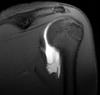

Diagnosis?

Os trigonum syndrome